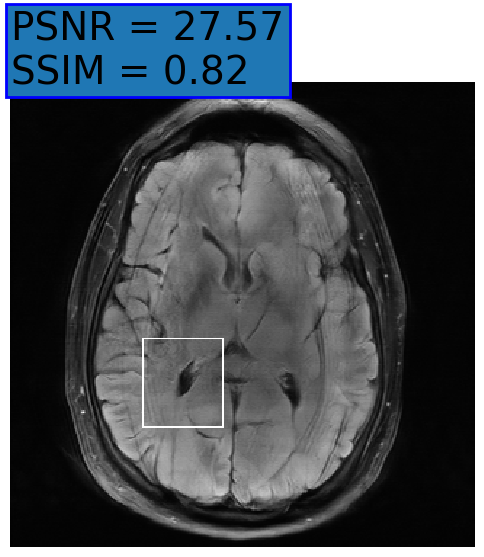

Figure 3: Reconstructions results. Rows 1 and 3: Examples of comparing the ground truth (GT) fully sampled image to the reconstructed images obtained by the three models (1-3), NPB-REC, baseline, E2E-VarNet trained with Dropout, and the NPB-REC std. map at accelerations R=4𝑅4R=4, R=8𝑅8R=8, respectively. Rows 2 and 4: The corresponding annotated ROIS of Nonspecific white matter lesions.

Fig. 3 presents examples of reconstruction results obtained by (1) our NPB-REC approach, (2) the baseline, and (3) Monte Carlo Dropout, for equispaced masks with two different acceleration rates R=4𝑅4R=4 and R=8𝑅8R=8. The reconstructed images predicted by the three models are smoother than the reference image. This is due to the fact that all the models were trained with SSIM loss, which tends to produce overly smooth reconstructions while preserving the diagnostic content and the anatomical features Sriram et al. (2020a). These images can be enhanced by dithering the image by adding a small amount of random Gaussian noise to produce a more textured reconstruction, as proposed in Sriram et al. (2020b).

Table 1 presents the mean PSNR and SSIM metrics, calculated over the whole inference set, for the three models. Our NPB-REC approach achieved significant improvements over the other methods in terms of PSNR and SSIM (Wilcoxon signed-rank test, pmuch-less-than\ll1e-4, except for SSIM values in line W, R=4𝑅4R=4 where they are roughly the same for NPB-REC and Baseline). The improvement in the reconstruction performance can be noted both quantitatively from the metrics, especially for masks with acceleration rate R=8𝑅8R=8, and qualitatively via the images of annotations, where our results show less smoothness than those obtained by Dropout.